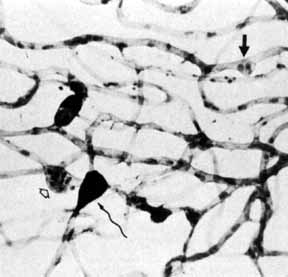

Although microaneurysms are the first ophthalmoscopically detectable change in diabetic retinopathy, the earliest abnormalities seen histopathologically are thickening of the capillary basement membrane1,2 and pericyte dropout.3,4 Pericytes are mesothelial cells that surround and support the retinal capillary endothelial cells. Normally there is one pericyte per endothelial cell. In people with diabetes, however, the pericytes die off and are decreased in number (Fig. 1). Their absence weakens the capillaries and permits thin-walled dilatations, called microaneurysms, to develop. Later, endothelial cells proliferate and lay down layers of basement membrane material. Fibrin may accumulate within the microaneurysm along with erythrocytes, and the lumen of the microaneurysm may become occluded (Fig. 2). Initially, most microaneurysms are on the venous side of the capillaries, but later they are seen on the arterial side as well. Clinically, they appear as small red dots (Fig. 3). Despite the multiple layers of basement membrane, microaneurysms are permeable to water and large molecules, allowing the transudation of fluid and lipid into the retina.

Fig. 1 A. Trypsin digest preparation of early background retinopathy. Normal retinal capillaries, with one pericyte (closed arrows) per endothelial cell (open arrows). B. Retinal capillary of a patient with diabetes with necrotic pericytes (arrows). (Courtesy of Dr. Myron Yanoff)

Fig. 2 Trypsin digest preparation of early background retinopathy. Early microaneurysm (closed arrow), aneurysm with endothelial proliferation (open arrow), and aneurysm occluded with fibrin (curved arrow). (Courtesy of Dr. Myron Yanoff)